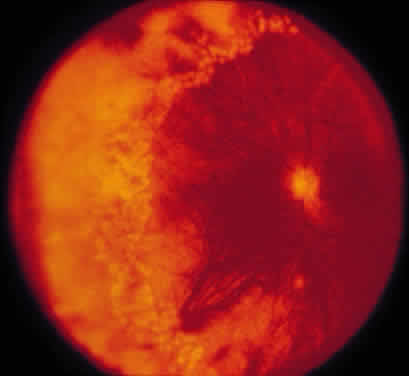

ARN is characterized by a retinal vasculitis affecting both the arteries and veins in the fundus, which is manifested by sheathing of the larger vessels (Fig. 2).7–10,16 Initially, patchy areas of peripheral retinal whitening (“thumbprint lesions”) representing full-thickness retinal necrosis are present or develop shortly after the vasculitis (Fig. 3). During a course that may span days or weeks, these patches coalesce into geographic areas (Fig. 4A). The entire peripheral retina (360 degrees) may be involved, or, more commonly, there are several noncontiguous patches of necrosis, each covering from a half to three clock hours (Figs. 5 and 6). The posterior segment lesions may not be detected without examination of the peripheral retina.

Intravenous fluorescein angiography may be helpful in delineating the extent of infection and elucidating the cause of central visual loss. In the early frames, choroidal perfusion defects may be seen; these defects are caused by areas of focal choroidal inflammatory cell accumulation and overlying retinal pigment epithelial damage (Fig. 16). Such choroidal perfusion defects may occur away from zones of active necrosis.42 Acute obstruction of the central retinal artery or any of its branches may be present. Peripheral views in the areas of active retinitis commonly show little or no intravascular fluorescein in the retinal arteries and veins. Often an abrupt “cut-off” of the intravascular fluorescein may be apparent at the edges of the retinal inflammation (see Fig. 4B and C). Areas of active retinitis show blockage of the underlying choroidal fluorescein pattern (see Fig. 7B). Recirculation phase views may reveal macular leakage, optic disc, and retinal vasculature staining.